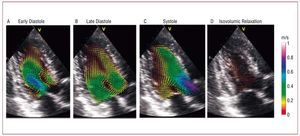

Experimental studies based on phase-contrast MR (PCMR)154-157 and echocardiography,158-163 have described the complex flow patterns inside the human left ventricle (LV). Figure 10 illustrates these patterns by displaying a sequence of maps of blood velocity in a healthy volunteer during early diastole (panel A), late diastole (panel B), systole (panel C), and isovolumic relaxation (panel D). The blood velocity vectors were imaged in the apical 3-chamber view of the LV and the anatomical images overlaid. At the onset of ventricular filling, the main flow pattern is the mitral starting jet, which is flanked by 2 counter-rotating swirling regions. The latter are the traces of a ring of vorticity associated with the mitral jet, whose 3D-structure is shown in Figure 11A, where the red loop represents the vortex ring and the arrows represent blood velocity. This vortex soon loses its symmetry because the part that is more proximal to the LV wall quickly decays under the effect of viscous dissipation. As a result, the flow at the end of diastole is dominated by a large single swirling pattern that is located close to the tip of the anterior leaflet of the mitral valve (Figure 10B). The 3D organization of the flow at this stage of the cardiac cycle is shown Figure 11B. The swirling region in the LV grows in size during diastole and can still be observed during the early stages of systole (Figure 10C), although it decays soon after the beginning of ejection. Studies using numerical simulation164-137 and in vitro experiments168-171 have confirmed this behavior.

Figure 10. Blood velocity mapping in a normal left ventricle overlaid on a sequence of anatomical B-mode apical long-axis images during (A) rapid filling, (B) late filling (C) ejection onset, and (D) isovolumic relaxation. The vectors indicate the direction and magnitude of the velocity as coded in the color bars (m/s).